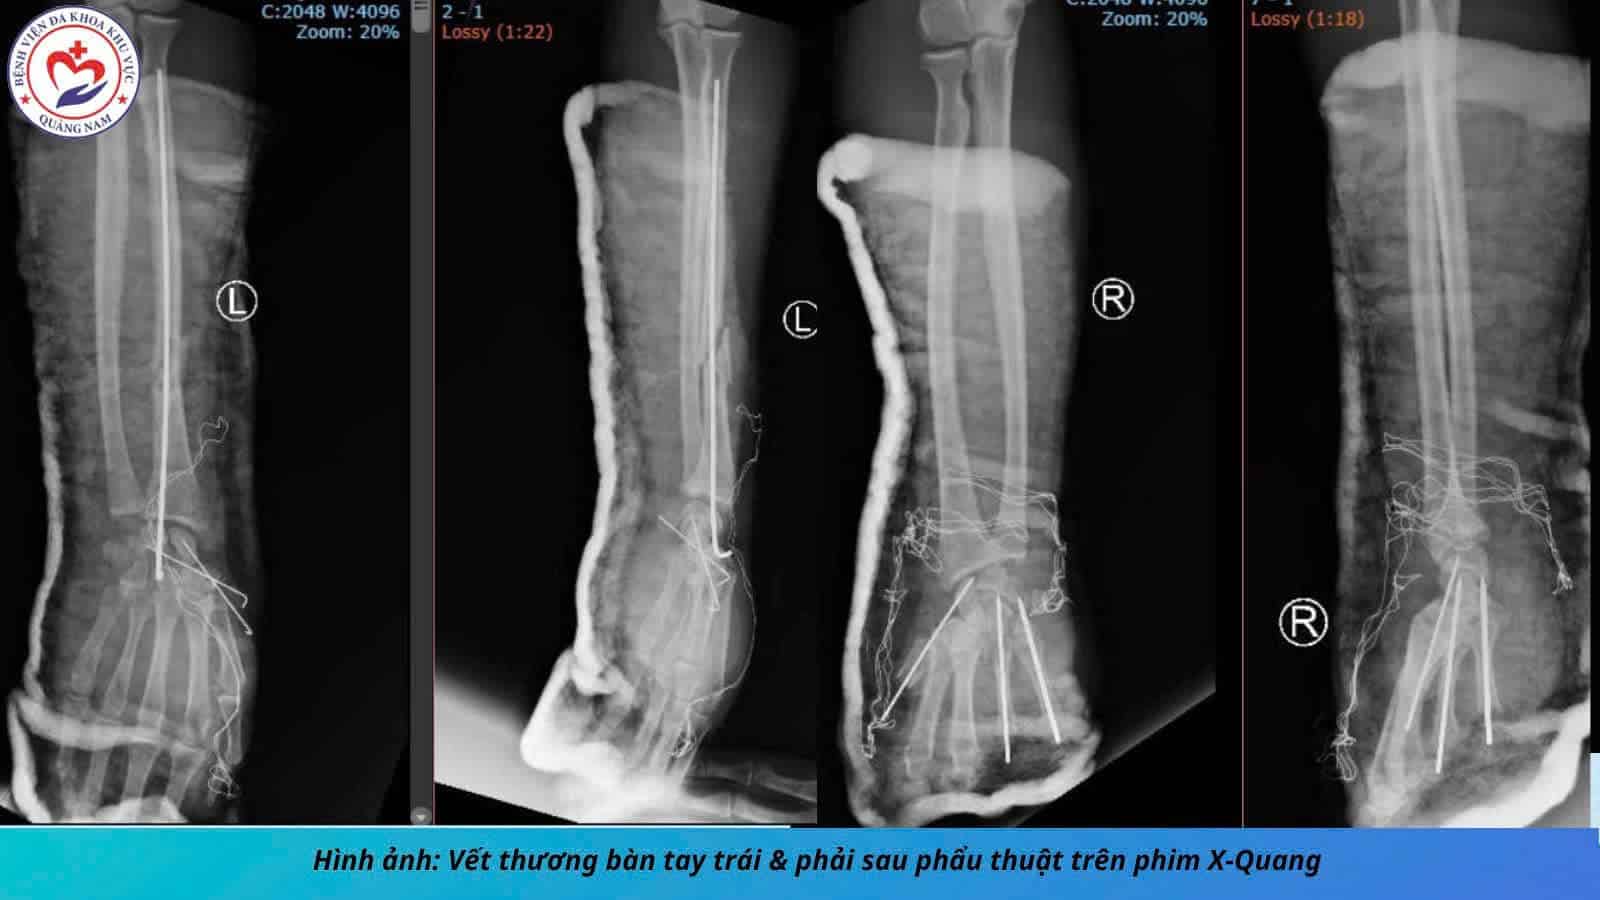

456 trường hợp khám, cấp cứu do pháo nổ, pháo hoa; 44 trường hợp khám, cấp cứu tai nạn do vũ khí, vật liệu nổ tự chế, chưa ghi nhận ca tử vong.